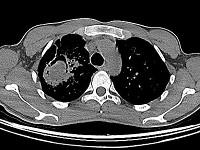

问题 男,32岁,咯血,咳痰一周,胸部CT如图,最可能的诊断为 ( )

选项 A、右上肺结核性空洞并霉菌感染 B、组织胞浆菌病 C、周围型肺癌 D、右上肺感染 E、肺结核

答案 A